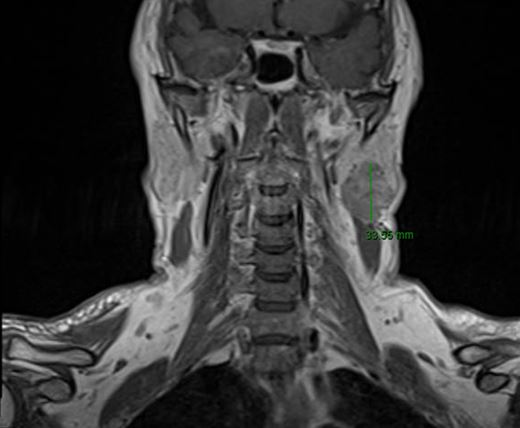

Hiện nay có nhiều phương pháp xét nghiệm giúp phát hiện sớm tình trạng u tuyến nước bọt mang tai như siêu âm, phim cắt lớp vi tính, cộng hưởng từ,… Việc thăm khám sớm và kịp thời điều trị có vai trò quan trọng trong việc giảm tỉ lệ tiến triển ác tính của u tuyến nước bọt mang tai.

Hình 3. Hình ảnh cộng hưởng từ hỗ trợ chẩn đoán u tuyến nước bọt mang tai